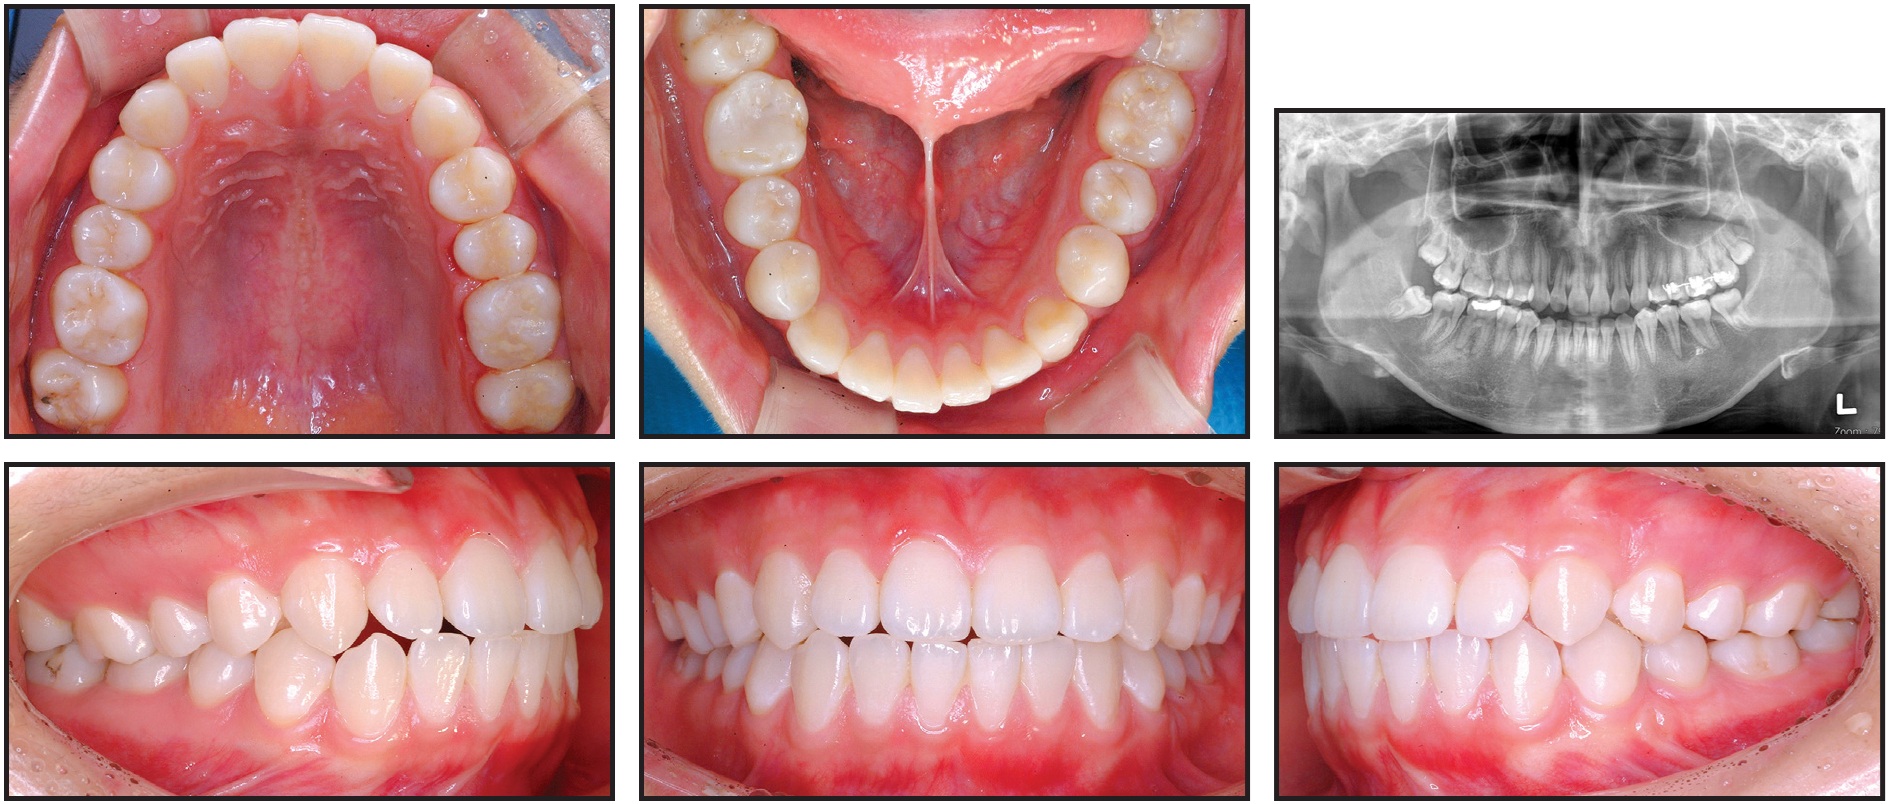

Fig. 11 Case 2. Patient after 27 months of treatment.

Total treatment time was 27 months (Fig. 11). The post-treatment records showed the gingival cleft between the second premolar and the protracted second molar, bone resorption in the mesial part of the second molar, and apical root resorption of the protracted second molar. In addition, bone atrophy in the buccolingual dimension was observed in the bone between the second premolar and the second molar.